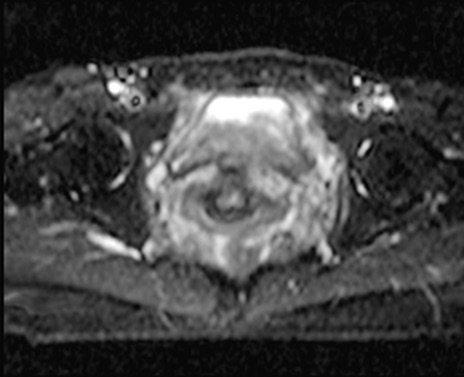

MRI(4日後)